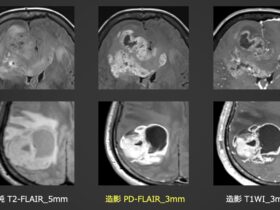

AIRS MEDICAL社のSwiftMRの検証